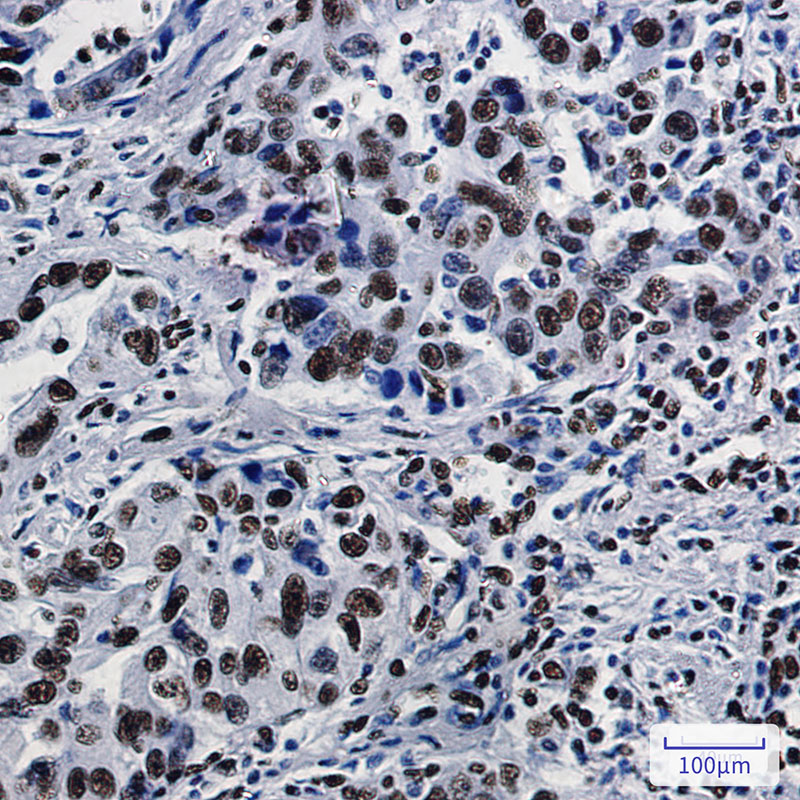

• Immunohistochemical analysis of paraffin-embedded human lung cancer tissue using db12226 antibody.